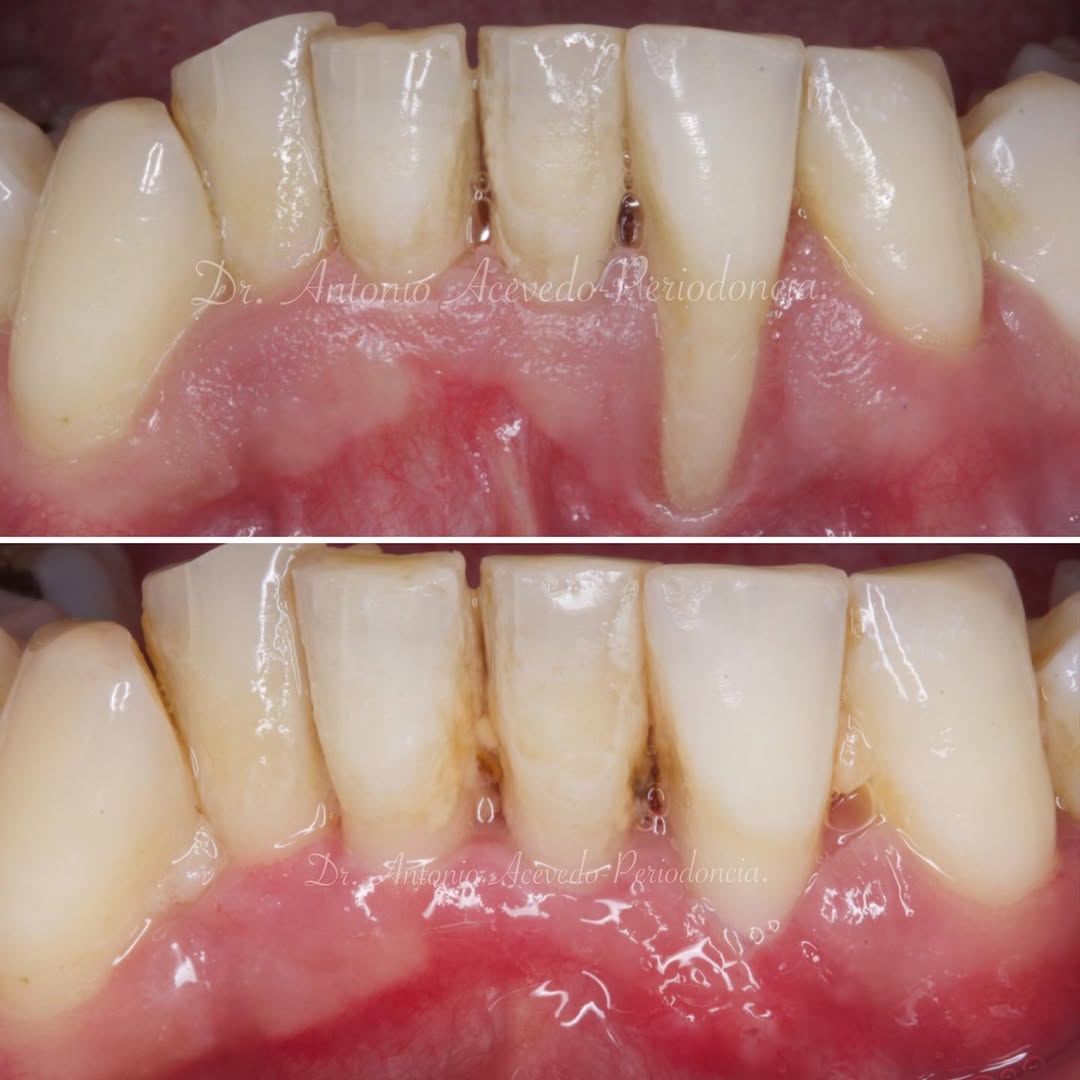

Durante una mañana, asistirás a una Cirugía Mucogingival de recubrimiento radicular de recesiones múltiples en IV y V sextante (36 a 43).

Gracias al uso del microscopio y a la proyección en tiempo real en pantalla, verás exactamente lo mismo que veo yo durante la cirugía, sin tener que estar

Aprende la planificación y técnica de la cirugía Mucogingival para el recubrimiento de recesiones y aumento de banda queratinizada en el sector anteroinferior